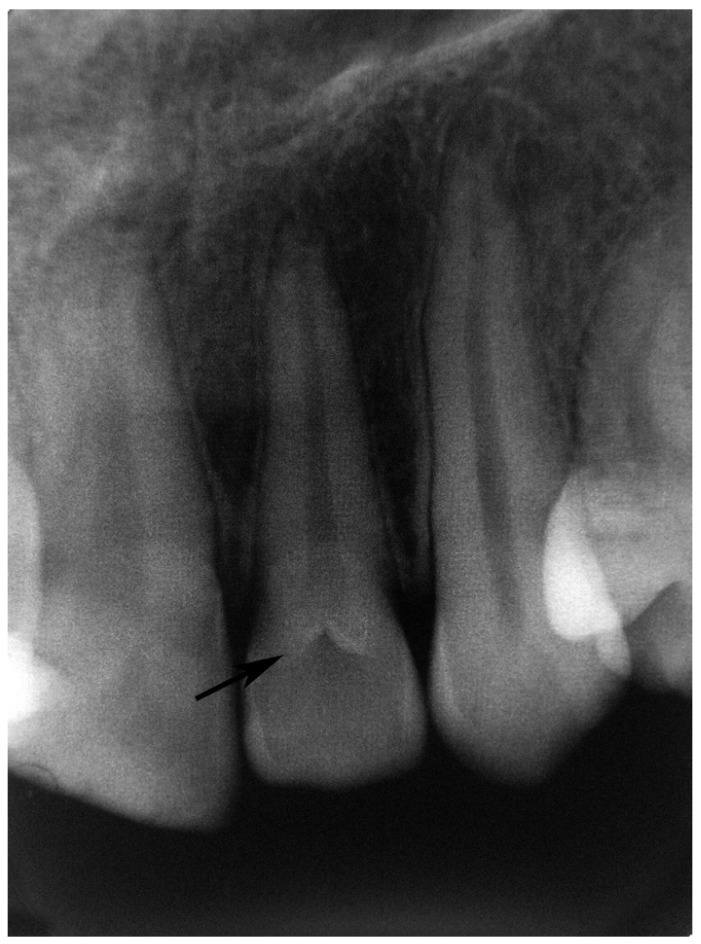

patient walks in and radiographs shows a tooth growing inside anotherl . what does this patient have? what causes this ? what tooth mostly found in?

dens invaginatus ( dens in dente)

caused by invagination of IEE

permanent maxillary lateral